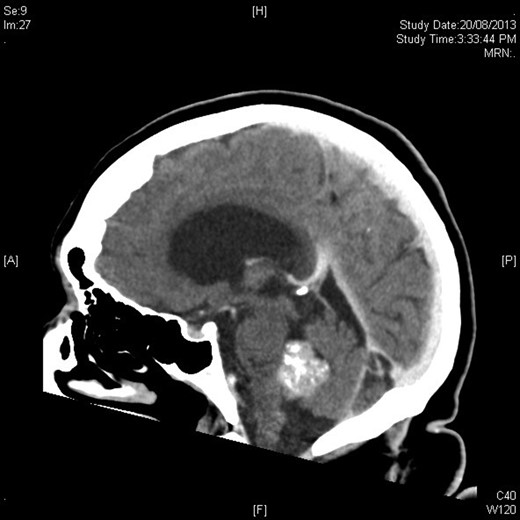

Mrs MM is a 62-year-old female who presented to our institution complaining of a 4-day history of nausea, vomiting and speech difficulties. She initially presented to a peripheral hospital following a fall at home and underwent workup for this. Clinically she scored a Glasgow Coma Scale (GCS) of 14 due to her confusion but had normal strength in all of her limbs. Initial computed tomography brain revealed a 2.6 × 2.5 × 2.1 cm rounded masses enhancing with contrast with areas of calcification in the fourth ventricle and obstructive hydrocephalus (Figs 1 and 2). The following day she underwent magnetic resonance imaging (MRI) brain showed the lesion to be isodense on T1-weighted imaging mildly hypodense on T2-weighted imaging (Fig. 3), and there was no other pathology demonstrated apart from chronic microvascular ischemic changes.

MRI sagittal T2 sequence with gadolinium showing rounded mass in fourth ventricle.